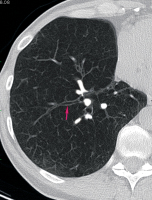

Computertomographie-COPD

Abbildung 3: Ektatisch erweiterte Bronchien des Unterlappens als Ausdruck einer Bronchopathie bei einer Patientin mit COPD